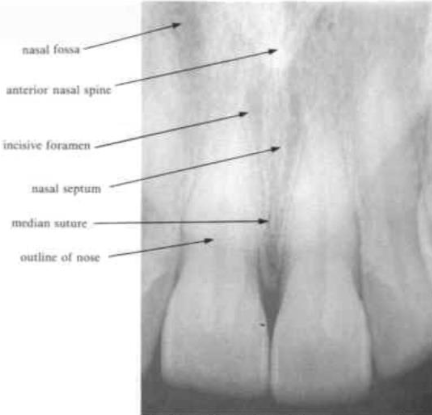

median suture

appears a radiolucent line between the central incisors in the maxilla

anterior nasal spine

appears as a V- shaped radiopacity which lies above or is superimposed on the incisive foramen

nasal septum

separates the two nasal fossae

is seen as a radiopaque white line

nose and lip line

is a definite line across the radiograph

a similar line in both upper and lower anterior radiographs often represents the lip line

incisive foramen

the radiolucent circular shadow of this foramen may be superimposed over the apex of a central incisor and so be mistaken for a periapical lesion